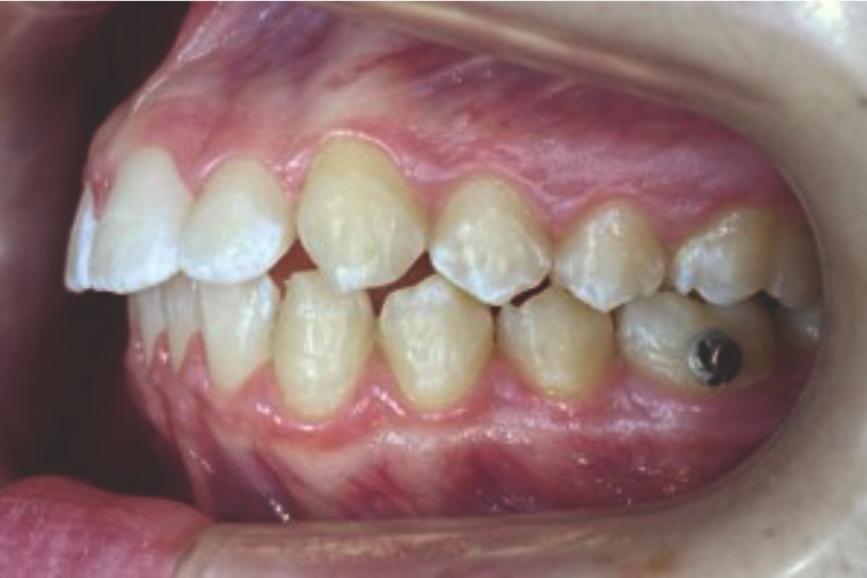

Chief complaint: We present the case of a 12-year-old female patient who came for an orthodontic evaluation, motivated by a family history of treatment. Clinical and radiographic analysis revealed a skeletal Class II malocclusion with molar and canine relationships also in Class II, moderate crowding in both arches, a deviation of the dental midline, and ectopic eruption of tooth 13. No functional issues with breathing or swallowing were observed, and oral health was generally good. A slight mandibular retrusion was noted in the soft tissue profile. A treatment plan was proposed using the Angel Aligner Pro system, aiming to correct dental misalignments and improve facial harmony through a minimally invasive, growth-adapted approach.

Clinical examination and diagnosis

- Woman ; 12/3 years

- Skeletal Class II

- Molar and canine Class II

- Upper and lower dentoalveolar compression

- Increased overjet and overbite

- Upper midline deviated 0,5 mm to the right

- Moderate upper and lower crowding